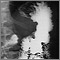

Antes de tomar las radiografías, usted tiene que tomar de 16 a 20 onzas (470 a 590 ml) de una bebida similar a una malteada que contiene una sustancia llamada bario, la cual se destaca muy bien en las radiografías.

Con un método radiográfico, llamado fluoroscopia, se rastrea la forma como el bario se desplaza a través del esófago, el estómago y el intestino delgado. Se toman imágenes con usted en diferentes posiciones. Puede estar parado o sentado.